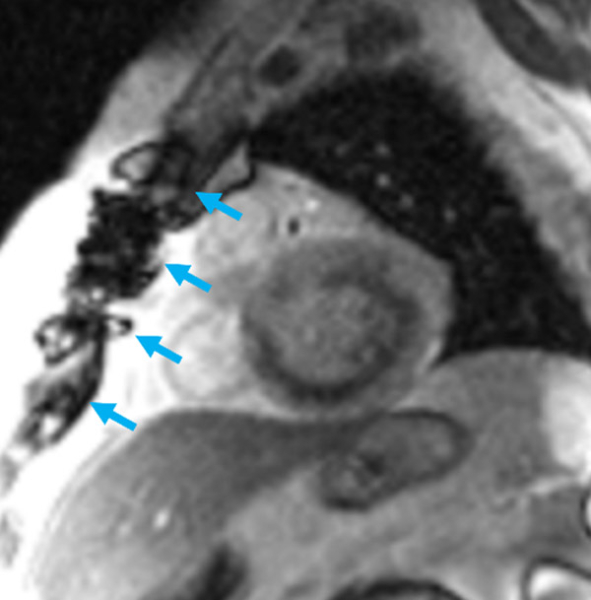

Bonus « le coup d’œil de l’imageur » : Fils de sternotomie

Vous pouvez voir sur l’image la présence d’artéfacts métalliques (flèches bleues) correspondant aux fils de sternotomie Important de noter que ces artéfacts ne posent aucun problème pour l’interprétation des images d’IRM cardiaque.